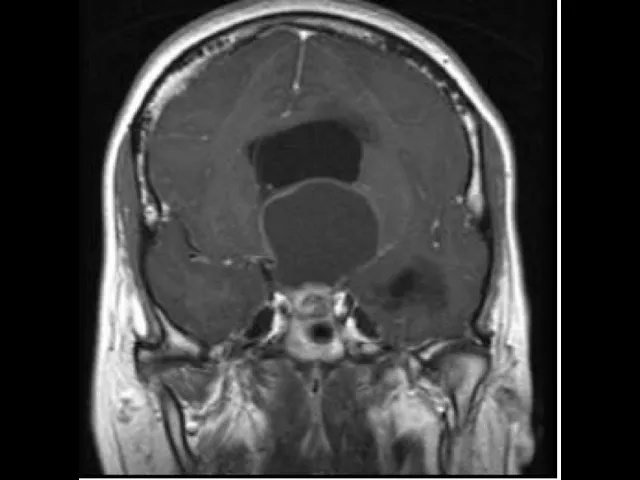

relação íntima com a hipófise a neuro-hipófise sendo uma continuação do infundíbulo hipotálamo e o exame de imagem na ressonância e se nós tomamos o corte sagital exatamente na linha média nós podemos observar aqui e o assoalho do terceiro ventrículo correspondendo ao encontrar a botar aqui um fundinho bruce continuando para compor a neuro impostos e eu vejo que há tumores que se desenvolvem nessa região é um tumor que afeta a região do hipotálamo é o craniofaringioma e foi assunto da minha tese de doutorado fiz pesquisa genética do crânio faringe oma tentando ajudar a obter mais meios

veja na imagem esse craniofaringioma uma porção sólida aqui na cela uma porção cística migrando para cima e acertou derrotarmos sem dúvida comprimido o seu plano provocando aí e no paciente assim não importa alegre é um s10 em algumas funções e estes eram alguns aspectos que nós gostaríamos de discutir de um modo bastante básico e objetivo sobre potara mas que já introduz a compreensão sobre a sua estrutura e a sua função espero que tenham aproveitar ficamos à disposição nos olhos meios de contato que é estão e até uma próxima oportunidade